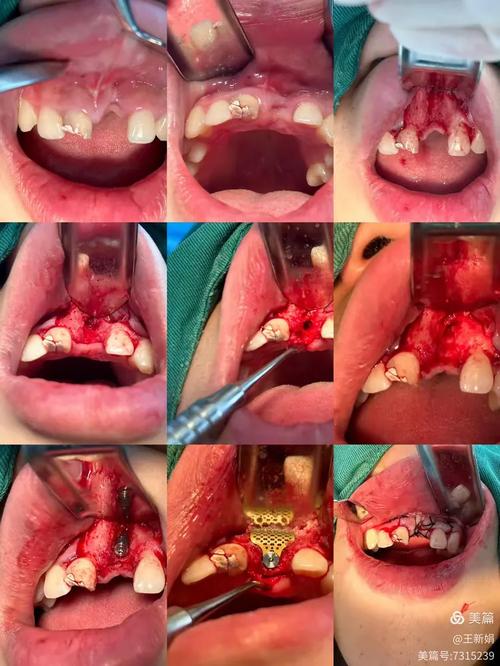

手术过程中,医生需切开牙龈、翻开牙龈瓣(即“翻瓣”),彻底清除牙根表面的牙结石、菌斑及病变的牙骨质,同时可能去除部分病变的牙槽骨,再植入骨粉引导骨再生,这些操作会对牙龈、牙槽骨及牙周韧带等软硬组织造成机械性损伤,术后局部组织会释放炎症介质(如前列腺素、白三烯),刺激神经末梢,引发疼痛。